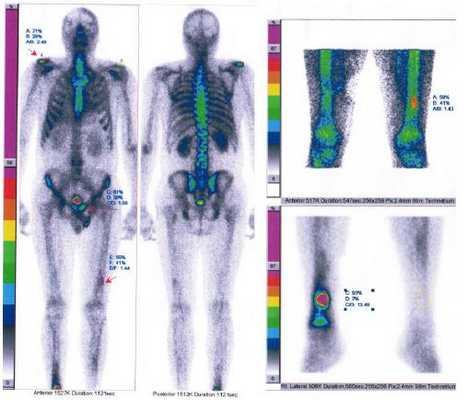

Обследование было направленно на выявление первичного опухолевого очага и распространенности онкологического процесса. При поступлении специфические жалобы (кардиалгии, ощущение аритмии, головокружения, одышка, неустойчивость АД) отсутствовали. Гемодинамика была стабильная. В связи с подозрением на вторичный характер изменений L4 была выполнена остеосцинтиграфия с 99mTc-пирфотехом, подтвердившая высокую вероятность вторичного опухолевого поражения костей скелета (рис. 1). Вечером 27.11.2016 г. произошло резкое ухудшение состояние в виде быстрого нарастания явлений острой сердечной (левожелудочковой) и дыхательной недостаточности. Пациент был переведён на вспомогательную вентиляцию лёгких и инотропную поддержку сердечной деятельности. По данным выполненных по cito трансторакальной эхокардиографии (рис. 2) и КТ-ангиографии (рис. 3) органов грудной клетки было выявлено объёмное образование левого предсердия, практически полностью заполняющее собой его полость и обтурирующее левое атриовентрикулярное отверстие. По неотложным показаниям в первой клинике хирургии (усовершенствования врачей) ВМедА в условиях искусственного кровообращения было выполнено удаление новообразования левого предсердия (рис. 4). В послеоперационном периоде явления острой сердечной и дыхательной недостаточности регрессировали. При гистологическом исследовании удалённого новообразования левого предсердия были выявлены признаки злокачественной мезенхимальной опухоли. Иммуногистохимическое исследование фрагмента опухоли позволило установить окончательный диагноз - «Недифференцированная плеоморфная саркома левого предсердия с прорастанием в межпредсердную перегородку и правое предсердие. Метастатическое поражение костей скелета: Th12-S2 позвонков, левой подвздошной кости, правой плечевой, лобковой, бедренной, большеберцовой костей».

Рис. 1. Результаты остеосцинтиграфии скелета с 99mTc-пирфотехом. Были выявлены зоны повышенного накопления препарата в проекции правого плечевого сустава (свыше 90%), в проекции лобковой кости слева (свыше 65%), в проекции нижней трети диафиза левой бедренной кости (свыше 35%), в проекции нижней трети правой голени (свыше до 97%). Зоны повышенного накопления препарата указаны стрелкой. Рис. 2. Трансторакальная эхокардиография (четырёхкамерная верхушечная позиция). В левом предсердии определяется объёмное образование, занимающее почти всю его полость (A, B) и пролабирующее в левый желудочек в диастолу с обструкцией атриовентрикулярного отверстия (C, D). Рис. 3. КТ-ангиография органов грудной клетки (фронтальная проекция).